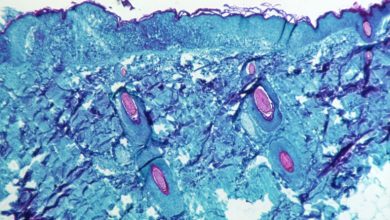

جدري القرود

“الصحة العالمية”: إصابات جدري القرود في العالم تقفز 20 بالمئة

واشنطن ترصد أول حالتي “جدري القرود” بين الأطفال

الصحة العالمية تدعو أوروبا إلى “تحرك عاجل” لمكافحة جدري القرود